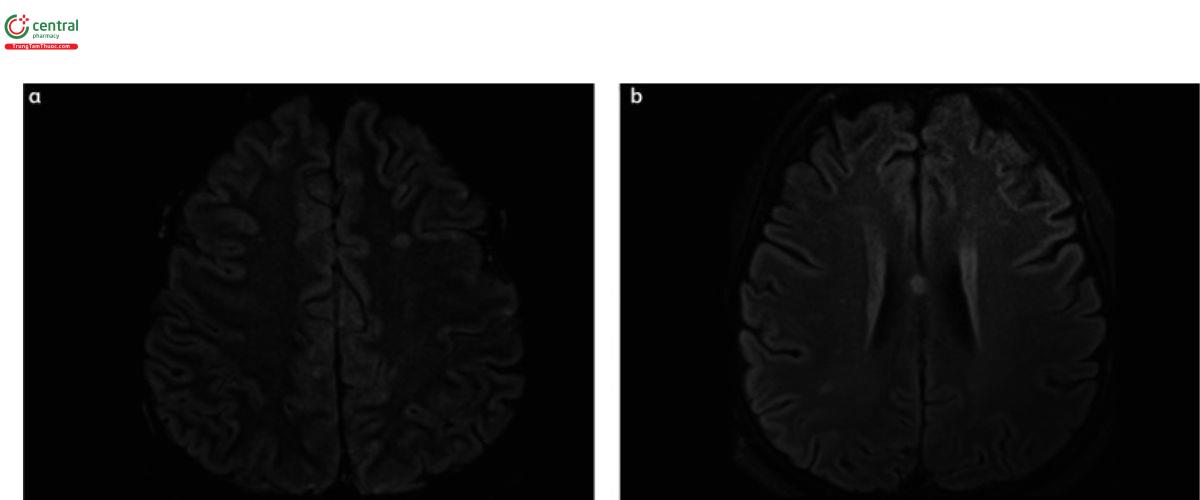

Chụp cộng hưởng từ (MRI) khuếch tán trọng lượng (DW) có thể cung cấp bằng chứng X quang hữu ích trong việc chẩn đoán viêm não Nipah.

MRI trong viêm não Nipah cấp tính cho thấy các tổn thương riêng biệt đa ổ có thể do các vùng nhồi máu nhỏ. Những tổn thương riêng biệt có cường độ tín hiệu cao này thường có kích thước khoảng 2-7 mm và phân tán khắp não, chủ yếu ở chất trắng dưới vỏ và sâu của bán cầu đại não. Hiệu ứng khối hoặc phù nề thường không được nhìn thấy.

Trong trường hợp tái phát hoặc viêm não Nipah khởi phát muộn, với hình ảnh thần kinh của họ minh họa các tổn thương vỏ não tăng tín hiệu lan rộng, có thể là kết quả của tổn thương vi tắc mạch kéo dài do viêm mạch

(b) Hình ảnh MRI DWI minh họa nhiều vùng tăng tín hiệu hai bên